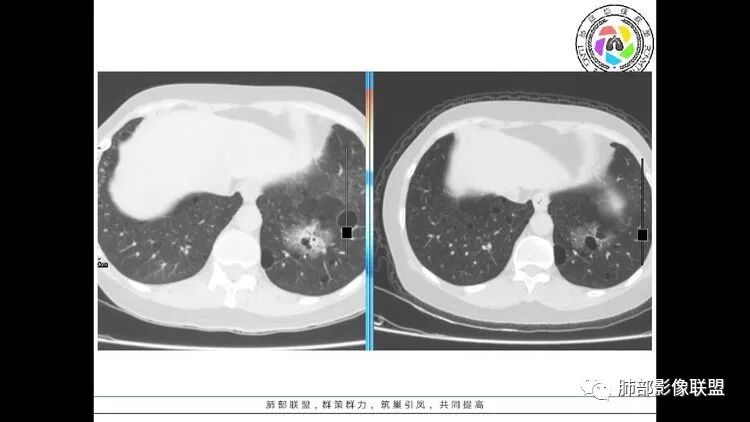

左肺下叶混杂密度病灶,其内可见空泡,周围ggo清楚,考虑浸润性腺癌。双肺散在多发薄壁囊腔和实性结节,以胸膜下及血管旁分布位于,气囊可见血管贴边征,双肺小叶间隔及中央间质增厚,局部可见磨玻璃影及树芽征,纵隔内淋巴结肿大,考虑LIP

综上,考虑左下肺浸润性腺癌+LIP

双肺多发大小不等囊腔,可见薄壁,部分囊腔内可见血管影,伴双肺多发结节,结合患者眼病及类风湿病史,考虑LIP可能大。另左肺下叶磨玻璃结节,边界清晰,内可见空泡,伴纵膈多发肿大淋巴结,不除外浸润性腺癌可能。

常规分析:右眼红疼1天,滴眼史两年,有类风湿病史,考虑有干燥综合征(SS)可能,需要了解自免抗体检测情况,双肺囊变需要考虑LIP,另右上叶前段GGO要鉴别腺癌或转移可能,右下叶背段多发树芽改变,双肺多发实性小结节,结核?左下肺混合性GGO考虑侵润性腺癌可能,双侧胸膜下多发结节,部分合并GGO改变,右侧腋窝及纵隔淋巴结多见,转移?最后问题来了,这个病人一元(腺癌合并转移,包括整个囊变,实性结节,胸膜下都是转移)?二元(LIP合并腺癌伴转移或者淀粉样变基础上的LIP)?三元(LIP+结核+腺癌伴转移)?

双肺下叶分布为主的间质改变(磨玻璃影、小叶间隔增厚)、散在气囊影(常有血管贴边)、边界不清小结节